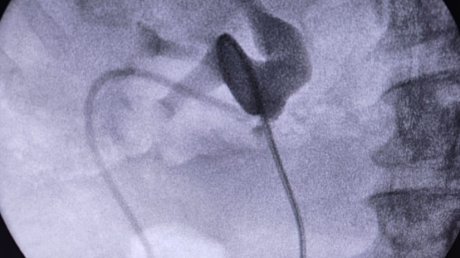

«Для его обнаружения в разрез стенки лоханки был проведен тонкий фиброуретеронефроскоп, который позволил выполнить инспекцию полостной системы почки и мочеточника», - рассказал Михаил Миронов.

Далее конкремент удалили и установили в мочеточник стент для дренажа.